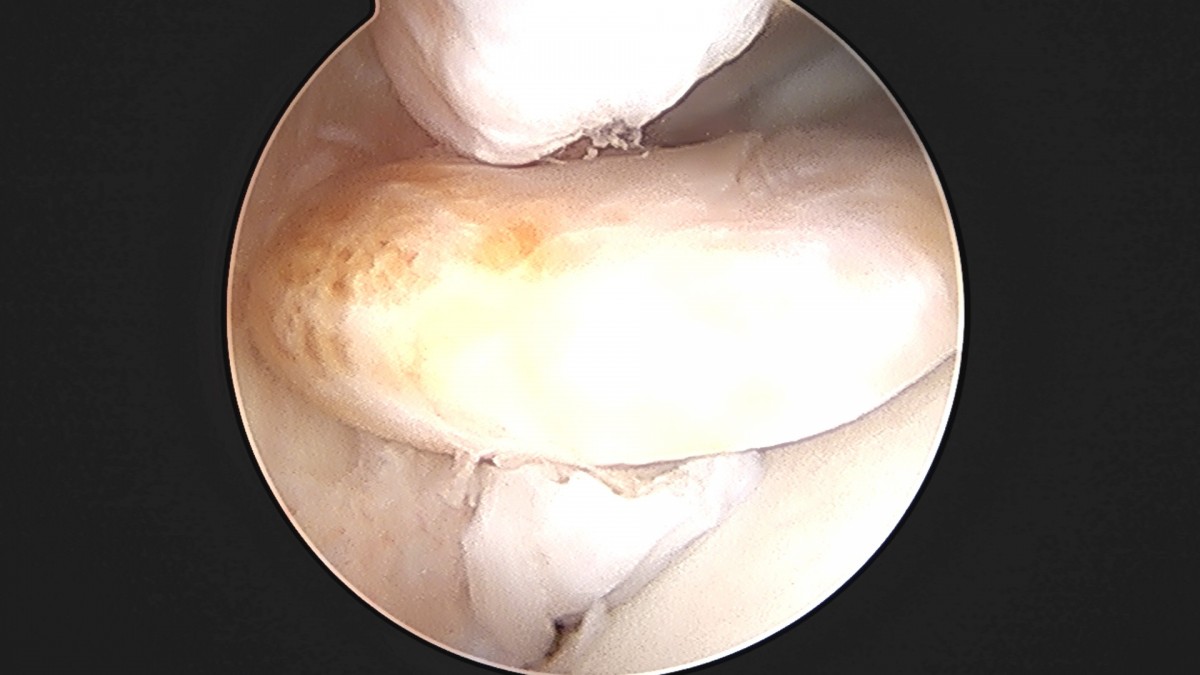

이재상원장님 발목 활액막 절제술 및 인대 봉합술 정보O 환자

dae765e4d9ac96aee867c9d6292d8784_1758003798_9553.jpg